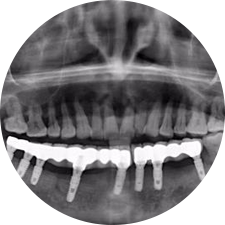

口腔種植是將人工牙根通過手術(shù)植入牙骨內(nèi),獲得牙槽骨牢固的支持,通過特殊的裝置和方式連接牙修復(fù)體,獲得與天然牙功能、結(jié)構(gòu)以及美觀相似的效果。

河北惟德口腔醫(yī)院擁有國內(nèi)豐富的半口/全口、即刻負(fù)重種植案例,十八年案例跟蹤分析,總結(jié)梳理出的各種不同類型的種植案例,Nobel種植體系針對(duì)半口/全口缺牙患者,通過4-8顆種植體可快速達(dá)到牙齒重建,不僅植入種植體較少,節(jié)省費(fèi)用,手術(shù)時(shí)間更短。

術(shù)前患者CBCT口掃1:1三維重建,模擬手術(shù)過程及預(yù)測(cè)術(shù)后治療效果,確定每顆植體植入的適合的種植位點(diǎn)、深度及角度,有效避免損傷頜骨重要解剖結(jié)構(gòu),提高手術(shù)準(zhǔn)確度與安全性。

Noble口腔種植體系基本不受年齡限制,適用于缺牙修復(fù),也適用于牙槽骨萎縮、骨質(zhì)疏松、高血壓、糖尿病、超高齡的患者,即種即用,只需少量微小種植體,便可輕松微痛快速重建全口咬合,特殊力學(xué)設(shè)計(jì),針對(duì)許多年紀(jì)較大,骨質(zhì)條件差,身體耐受力差的缺牙老人也能完成“即種即用”,受到廣泛好評(píng)。

惟德口腔種植體系是以患者感受為中心,取代傳統(tǒng)種植牙手術(shù)需要翻瓣、打孔、縫合,術(shù)前、術(shù)中、術(shù)后的繁復(fù)流程,采用3D導(dǎo)航微創(chuàng)準(zhǔn)確種植技術(shù),通過數(shù)字化CAD/CAM掃描技術(shù)獲得缺牙患者口腔數(shù)據(jù),以數(shù)據(jù)為基礎(chǔ)重建口腔模型進(jìn)行模擬種植。

術(shù)前將患者口內(nèi)的CBCT數(shù)據(jù)及咬合關(guān)系上傳到計(jì)算機(jī)中,建立1:1三維重建,模擬手術(shù)過程及預(yù)測(cè)術(shù)后治療效果,找出較佳種植位點(diǎn)、深度及角度,獲取實(shí)際種植體在頜骨內(nèi)的具體三維位置,有效避免損傷頜骨重要解剖結(jié)構(gòu),大大降低手術(shù)風(fēng)險(xiǎn),提升種植成功率。